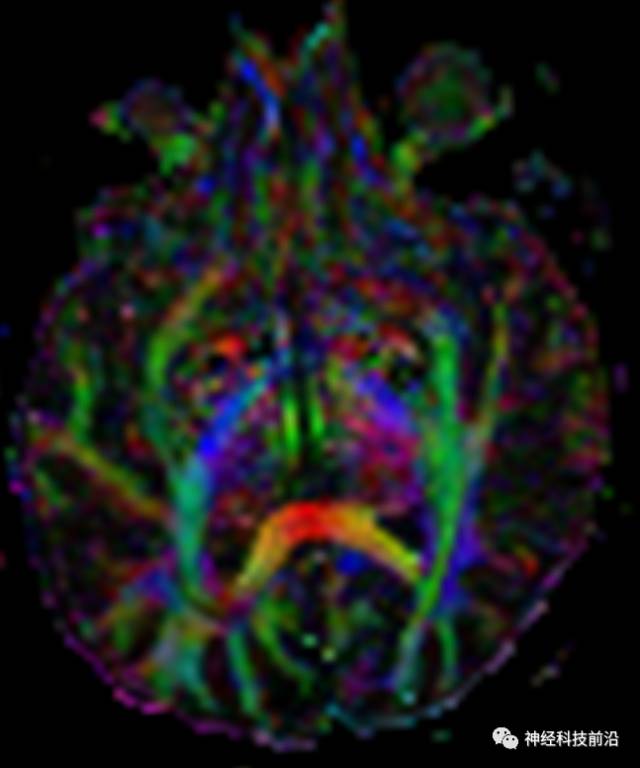

下面为皮质脑桥束的走形方位

皮质脑桥束与脑干高信号(黄色)纤维束